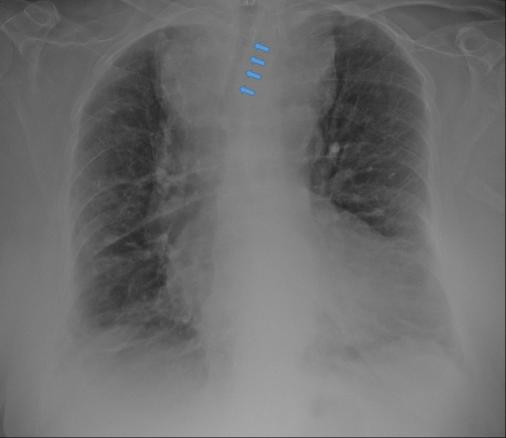

Radiographie thoracique d’un goitre plongeant. Les flèches indiquent la compression trachéale.

Extrait de : Conduite à tenir devant un goitre plongeant